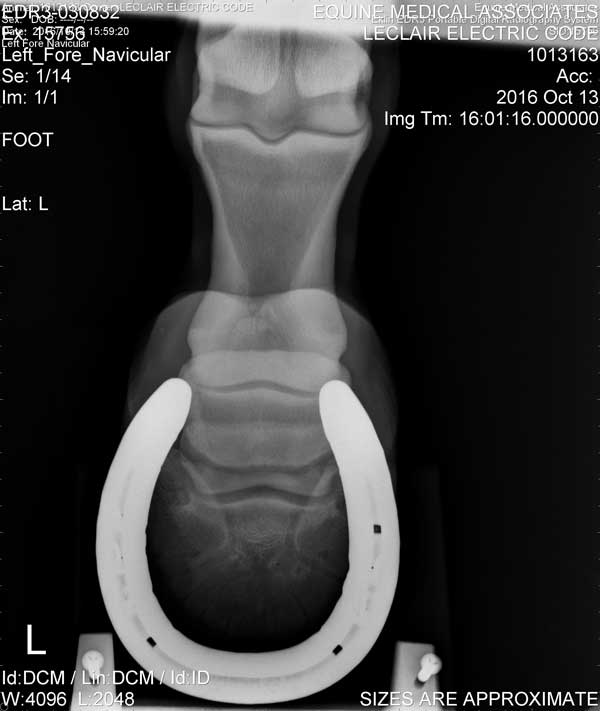

Hoof

Left